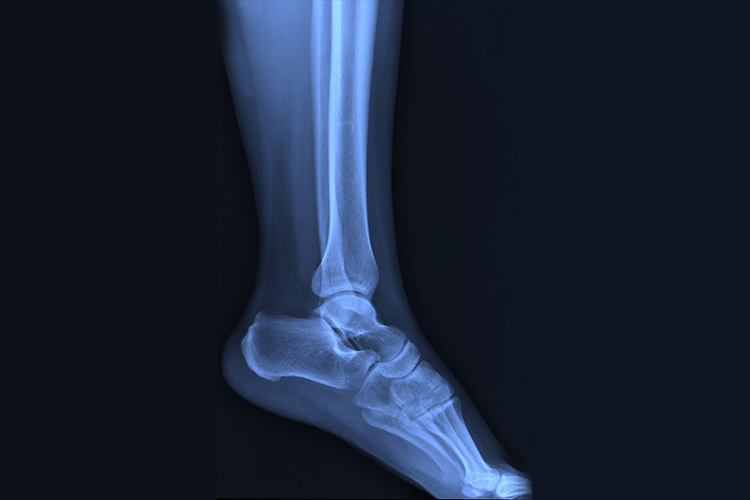

脚位于人体下肢末端,通过踝关节与胫骨、腓骨相接,为人类行走的重要组织。

脚位于人体下肢末端,由跗骨、跖骨和趾骨组成。跗骨共7块,属短骨。分前、中、后三列。后列包括上方的距骨和下方的跟骨;中列为位于距骨前方的足舟骨;前列为内侧楔骨、中间楔骨 、外侧楔骨及跟骨前方的骰骨。

跖骨共5块,由内侧向外侧分别为第1-5跖骨,形状和排列大致与掌骨相当,但较掌骨粗大。每一跖骨近端为底,与跗骨相接,中间为体,远端称头,与近节趾骨底相接。第5跖骨底向后突出,称第5跖骨粗隆,在体表可扪及。

趾骨共14块。拇趾为2节,其余各趾为3节。形态和命名与指骨相同。趾骨粗壮,其余趾骨细小,第5趾的远节趾骨甚小,往往与中节趾骨长合。

由于高处坠下或跳下时,足跟部先着地,可出现跟骨骨折,为足部好发疾病。患者可出现足跟部肿胀、跟骨内外侧瘀斑,可伴有剧烈疼痛和压痛,不能站立行走,严重者足弓变形。可通过手法整复外固定、跟骨结节牵引复位固定、切开复位固定等方法进行治疗。